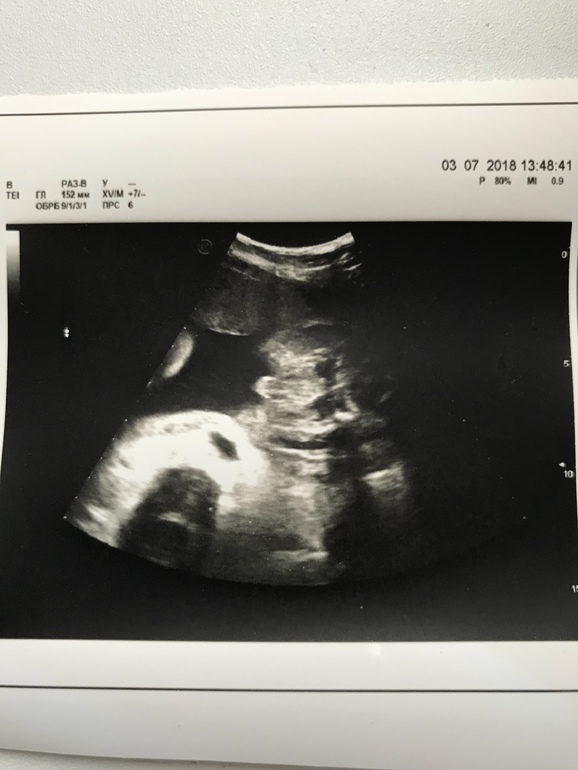

Пол малыша Привет, девочки! У нас неожиданно возникли сложности с определением пола малыша, в 20 недель сказали, что девочка, в 22 (было УЗИ по показаниям), что мальчик, в 29 сказали, что непонятно, то от девочка, то ли мальчик. Я запуталась 😳 Видимо, точно узнаем в сентябре только 😂 Но сейчас интересно порассуждать, как вы думаете, на кого больше похоже на девочку или мальчика? 😊

Я больше к мальчику склоняюсь. На первом фото хорошо видно, на втором если увеличить и присмотреться, тоже что-то виднеется похожее на яички. Просто ракурс не очень. Вот у нас девочка, фото ровно 16 недель, не к чему придраться, и сейчас в 21 неделю ходили, между ножек ничего не выпячивается :)